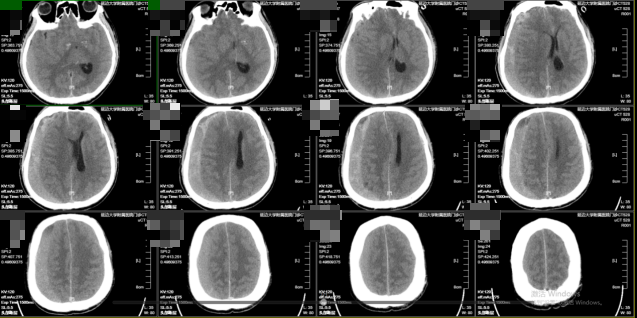

56岁男性患者,既往因患肝癌行手术治疗及脾脏切除术等。该患者因“突发意识不清、右侧瞳孔散大约1小时”为主诉于急诊入院。头部CT示右额颞顶枕部慢性硬膜下血肿,右侧侧脑室受压,伴中线结构左移>1.5cm,脑疝形成!左侧额部慢性硬膜下血肿。血栓弹力图:R(凝血因子活性)3.4min(偏低,5-10min为正常值),提示凝血功能异常,可能增加出血风险。

考虑患者高龄、基础状态差,特别是既往肝癌手术(影响凝血因子合成)及脾脏切除(可导致血小板计数及功能异常)导致的凝血功能紊乱,保守治疗风险极高且效果较差。黄宪主任医师、马吉男主治医师团队果断行右侧颅骨钻孔引流术(左侧给予保守治疗),术后瞳孔回缩,意识转清。术后密切监测病情变化。考虑其脾切除后存在凝血机制异常,血肿复发概率高,与家属沟通后进一步行经导管双侧脑膜中动脉(MMA)栓塞术,从而降低复发率。术后神清语明,四肢无瘫,顺利出院。1个月后复查头部CT右侧慢性硬膜下血肿明显减少,左侧慢性硬膜下血肿基本吸收。四肢肢体肌力V级。事实证明,经导管双侧脑膜中动脉(MMA)栓塞术治疗慢性硬膜下血肿效果显著,且依据文献报道可将复发率降至5%以下。

图1入院头部CT